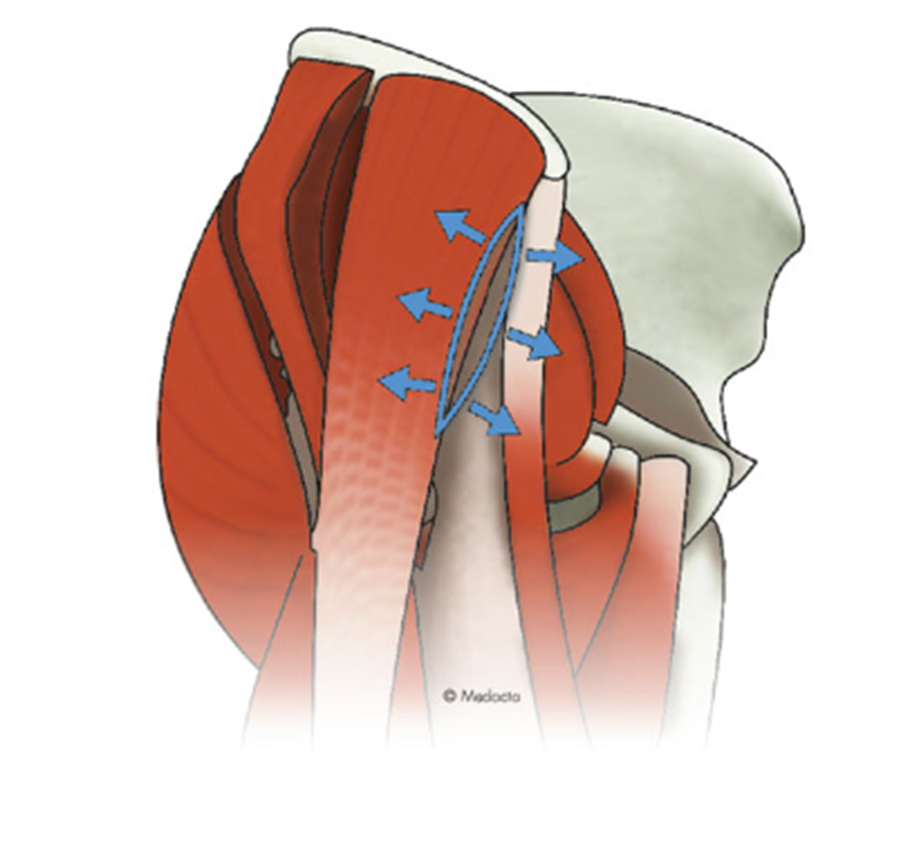

当院ではMISのなかでも特に侵襲が少ないといわれるAMIS(最小侵襲前方手術)という手技で人工股関節手術を行っています。

AMISは、専用の牽引手術台を使用して行う前方アプローチで筋肉をまったく切離せず、さらに関節周囲の軟部組織も極力温存する特殊な方法です。フランスで報告されて以来、世界的にも認められた非常に有用な手技ですが、誰にでも行える手術ではなく、ライセンス認定を受けた医師のみが行える手術手技です。体へのダメージや痛みも少なく、術後の早期回復や高い脱臼抵抗性(脱臼のしずらさ)に貢献しています。

股関節 断面